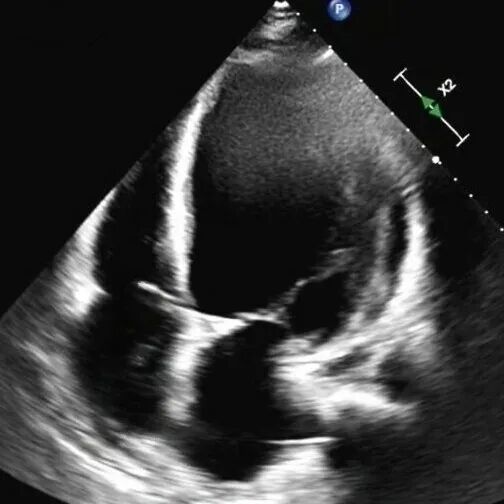

61岁的李先生(化名)三年前就偶尔出现胸闷乏力,一个月前,他因夜间无法平卧、呼吸极度困难,被紧急送往新疆医科大学第一附属医院(第一临床医学院)心脏重症监护室。通过系统检查,李先生左室舒张末期内径102mm(男性的正常值≤55mm),主动脉根部瘤样扩张63mm(正常≤35mm),左室射血分数仅21.83%(正常≥50%),心功能IV级(NYHA分级),主动脉瓣重度关闭不全,二尖瓣轻-中度关闭不全,最终确诊为终末期心衰,巨大心脏,主动脉根部瘤样扩张,随时发生主动脉夹层/主动脉破裂危及生命,此外主动脉瓣重度关闭不严,心功能极差,心脏随时可能“停摆”。

术前心脏超声